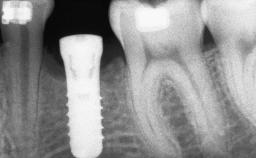

A 46-year-old woman was referred for treatment whose main complaints were mobility of her fixed partial dentures (right maxilla and left mandible) and periodontal bleeding during function. She also reported having taken systemic antibiotics to treat recurrent swelling in the area of the upper left molars. The patient had not seen a dentist for at least 2 years. She did not smoke and had no history of major systemic disease other than two minor orthopedic procedures some years back. The first-visit examination revealed poor plaque control, tooth mobility, periodontal disease, and a residual dentition widely associated with deep periodontal pockets.

| Bone Augmentation | Horizontal|Staged|Vertical |

| Bone Volume | Deficient vertically or deficient vertically AND horizontally |